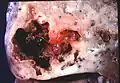

Pathology image of a lung abscess. -

Lung abscess is a type of liquefactive necrosis of the lung tissue and formation of cavities (more than 2 cm)[1] containing necrotic debris or fluid caused by microbial infection.